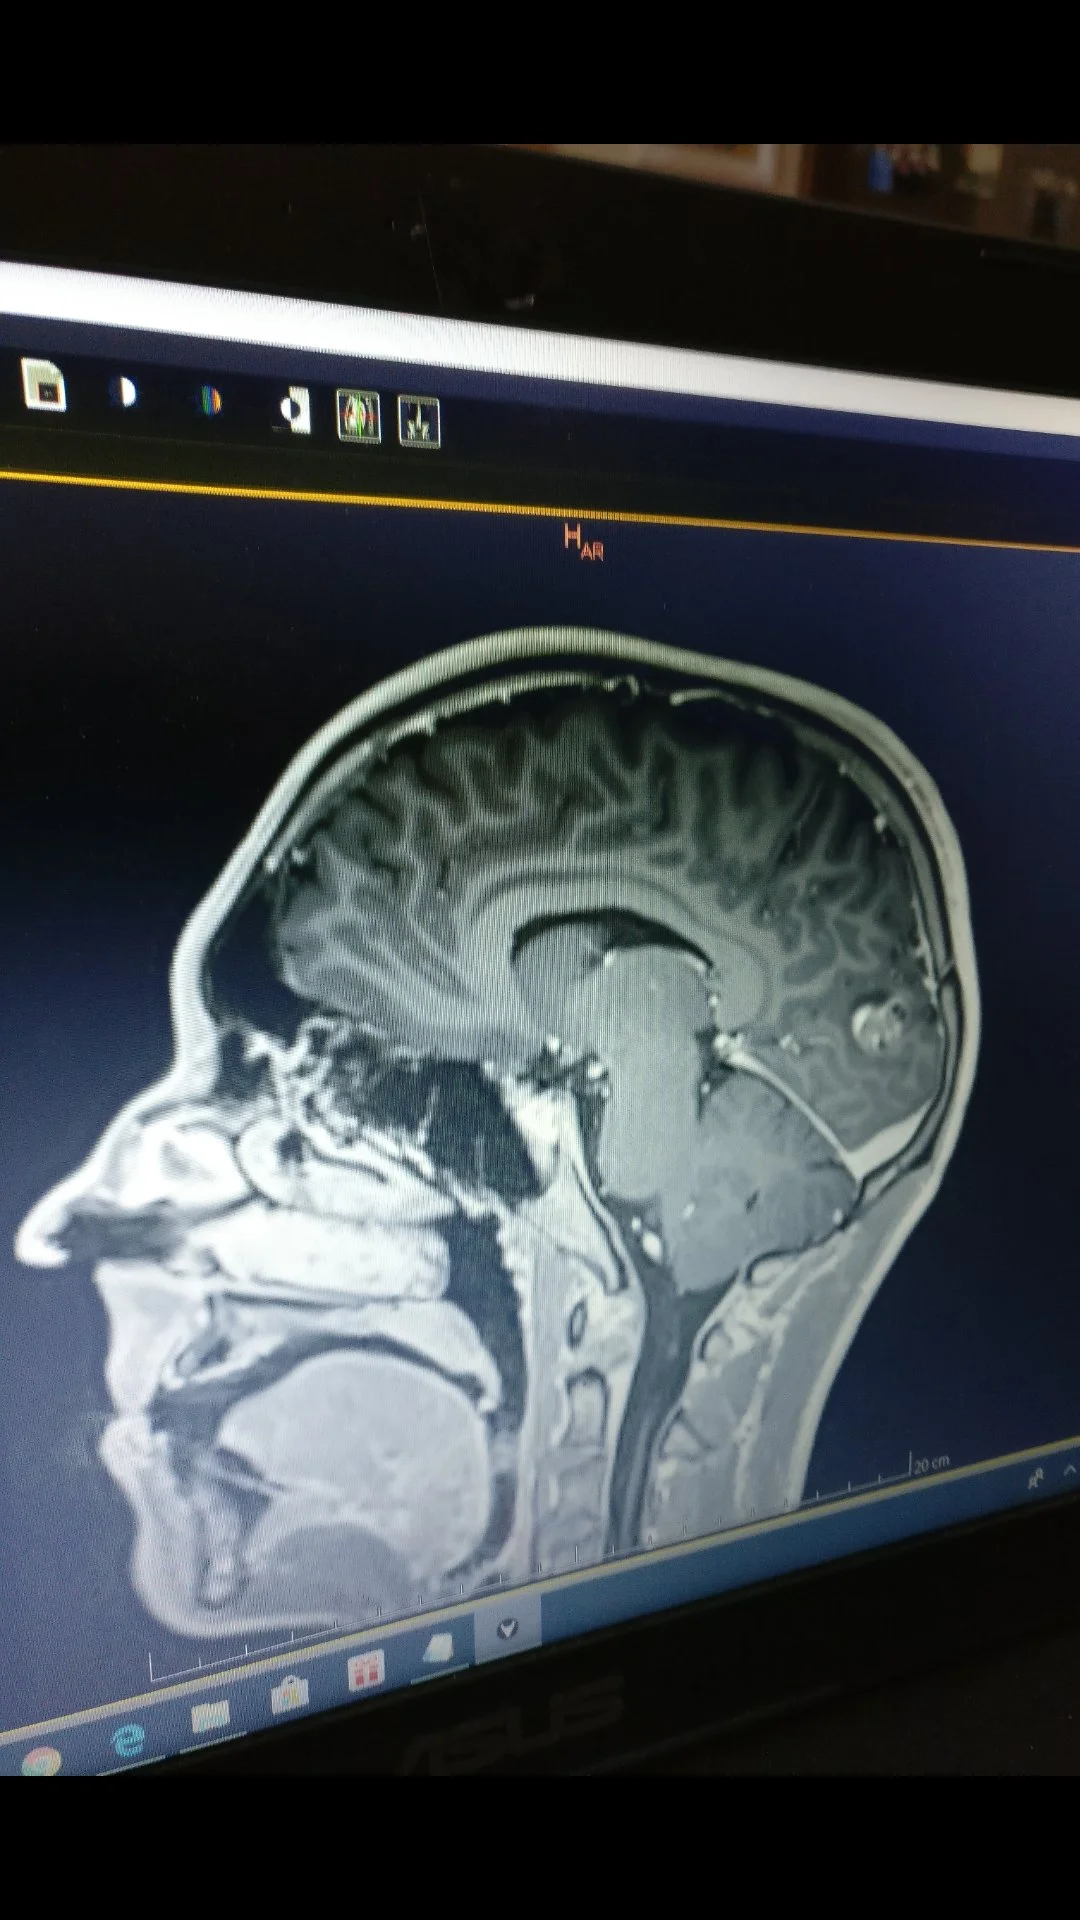

Reluctantly, I underwent three rounds of chemotherapy over nine weeks. A few months later, I suffered a seizure. An MRI revealed a new tumor growing in my brain, which was treated using Gamma Knife radiation.